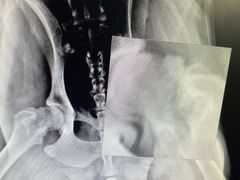

• 小叮当动物医院·骨科·眼科

报错

• -小叮当动物医院·骨科·眼科